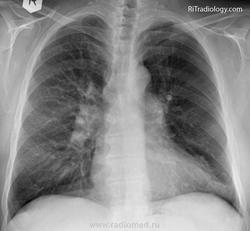

Swyer-James syndrome - эмфизема легких, при которой обычно поражается только одно легкое; болезнь чаще всего начинается в детстве или в юности. Развивается после перенесенного некротического бронхита и, по мнению специалистов, вероятнее всего, ее причиной является присутствующий в организме вирус.